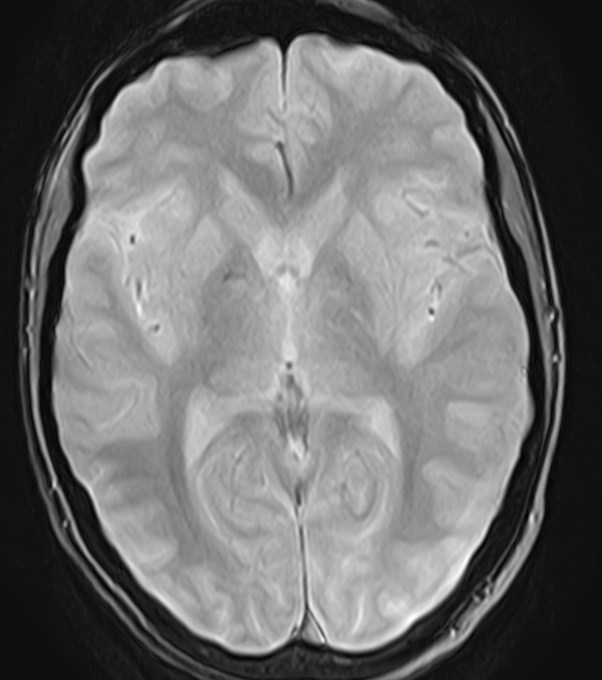

МРТ головного мозга является высокоинформативным методом исследования центральной нервной системы, который дает возможность оценить состояние всех структур головного мозга и поставить правильный диагноз. Стандартную МРТ головного мозга дополняет МР-венография, которая позволяет получить детальную картину строения и функционального состояния венозной системы мозга.

В клинике «Доступная медицина» проводится МРТ головного мозга и МР-венография головного мозга на современном аппарате TOSHIBA VANTAGE TITAN 1,5 Тесла, который обладает высокой чувствительностью и соответствует всем мировым стандартам качества диагностики. Напряженность магнитного поля 1,5 Тесла обеспечивает высокую четкость изображения и позволяет выявлять заболевания на ранних стадиях развития. Процедура МРТ безопасна, так как томограф не испускает рентгеновского излучения, полностью безболезненна и имеет доступную стоимость.

• очаги ишемического и геморрагического инсульта, область поражения, признаки отека головного мозга, стадию развития заболевания;

• доброкачественные и злокачественные новообразования, их точную локализацию, стадию развития процесса, проводить динамическое наблюдение за опухолевым процессом на фоне лечения;

• признаки демиелинизирующих заболеваний (рассеянный склероз), выявить очаги поражения миелиновой оболочки нервных волокон, определить стадию заболевания;

• характерные признаки дегенеративных заболеваний головного мозга (болезнь Альцгеймера, старческая деменция, болезнь Паркинсона), определить изменения коры головного мозга и подкорковых структур;

• поражение структур головного мозга на фоне травм, гематомы головного мозга;

• изменения, характерные для психических расстройств различного генеза (эндогенных и экзогенных), после вирусных инфекций, черепно-мозговых травм, отравлений токсическими веществами, на фоне наследственных заболеваний;